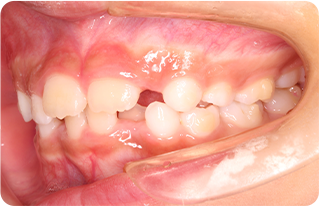

従来の矯正治療は顎の拡大と、一つ一つの歯を動かすことを別の時期に行っておりましたが、インビザラインファーストは、同時進行できるため、治療期間が他の治療法と比べて短期間で行えます。

一期に歯並びを整えることで、成長期に入る前に歯の位置を整えることができ、Ⅱ期治療が必要な歯並びの矯正に必要な期間が短縮できます。

一期治療で歯の土台を整え、顎の発育が正常に進むと、二期治療で抜歯や外科手術を必要とせずに歯並び矯正ができます。